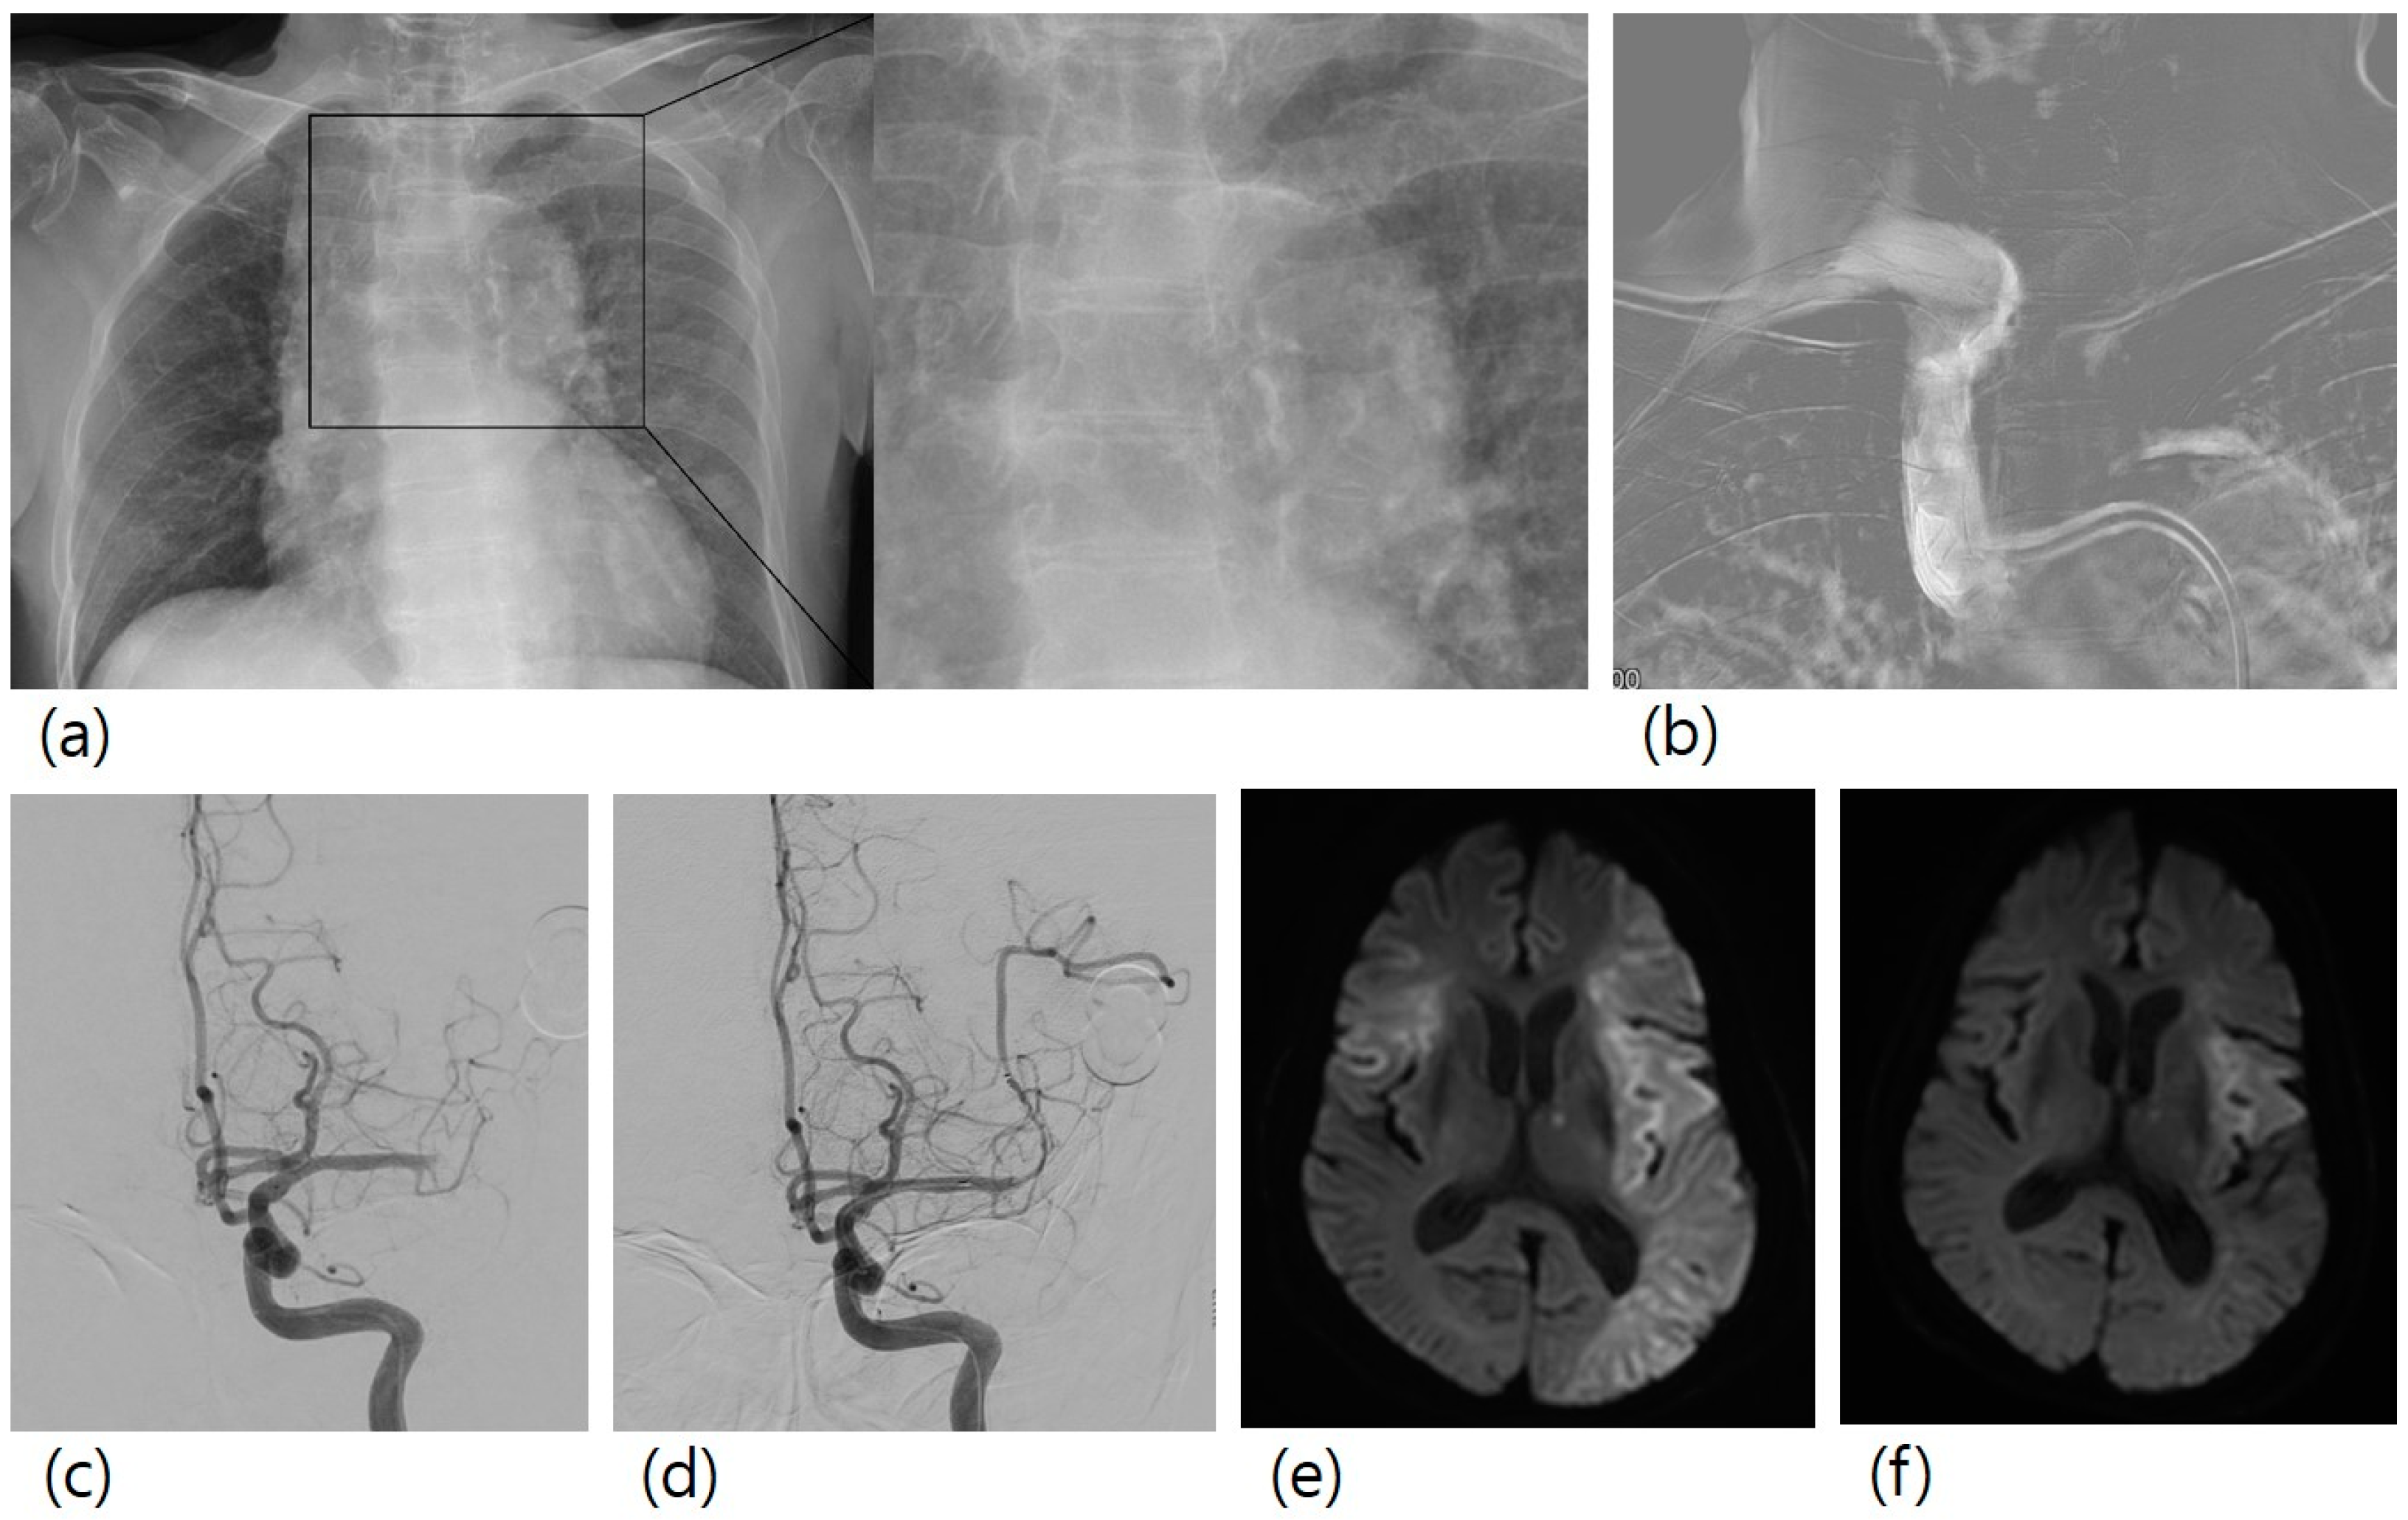

Stroke etiology was atherosclerotic occlusions (n = 38), cardioembolic occlusions (n = 49), others (n = 2), and unknown (n = 42). The overall rate of AoAC was 39.7% (n = 52). Procedural thromboembolism occurred in 30 (22.9%) patients. All the patients with procedural thromboembolism showed no newly developed neurological symptoms. One patient had a large-sized procedural thromboembolism, and the other 29 patients had multiple focal lesions. Figure 1 shows a case of a patient with a large-sized procedural thromboembolism.

Figure 1.

A case of mechanical thrombectomy for left M1 occlusion. A 78-year-old female patient with right hemiparesis visited our hospital. (a) Her chest X-ray showed aortic arch calcification. (b) In the first step of the procedure, guiding catheter was advanced to the brachiocephalic artery, and a roadmap image was obtained. (c) Left M1 occlusion was observed. (d) Mechanical thrombectomy with stent retriever was conducted, and successful recanalization was achieved. (e) Diffusion-weighted imaging two days after mechanical thrombectomy showed a new lesion in the right MCA territory, (f) which was not observed in diffusion-weighted imaging before mechanical thrombectomy.